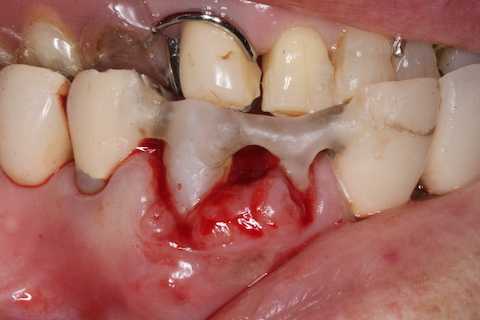

普通にズブズブと抜歯窩に再建した歯根を挿入する。

あとは接着固定しながら、歯冠を再建していく。